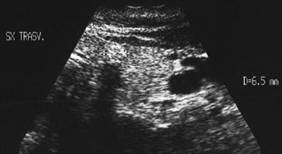

Sonda convexa de 5.0 MHz,

Sonda liniara de 10.0 MHz, proiectie trasversala si longitudinala a lobului

stang.

Pacienta de 28 ani. Voluminoasa tumefactie a lobului

stg., marcant hipoecogena, cu intarire posterioara, de 38x45x69mm.

La aspiratie, circa 60 cc de coloid foarte dens.